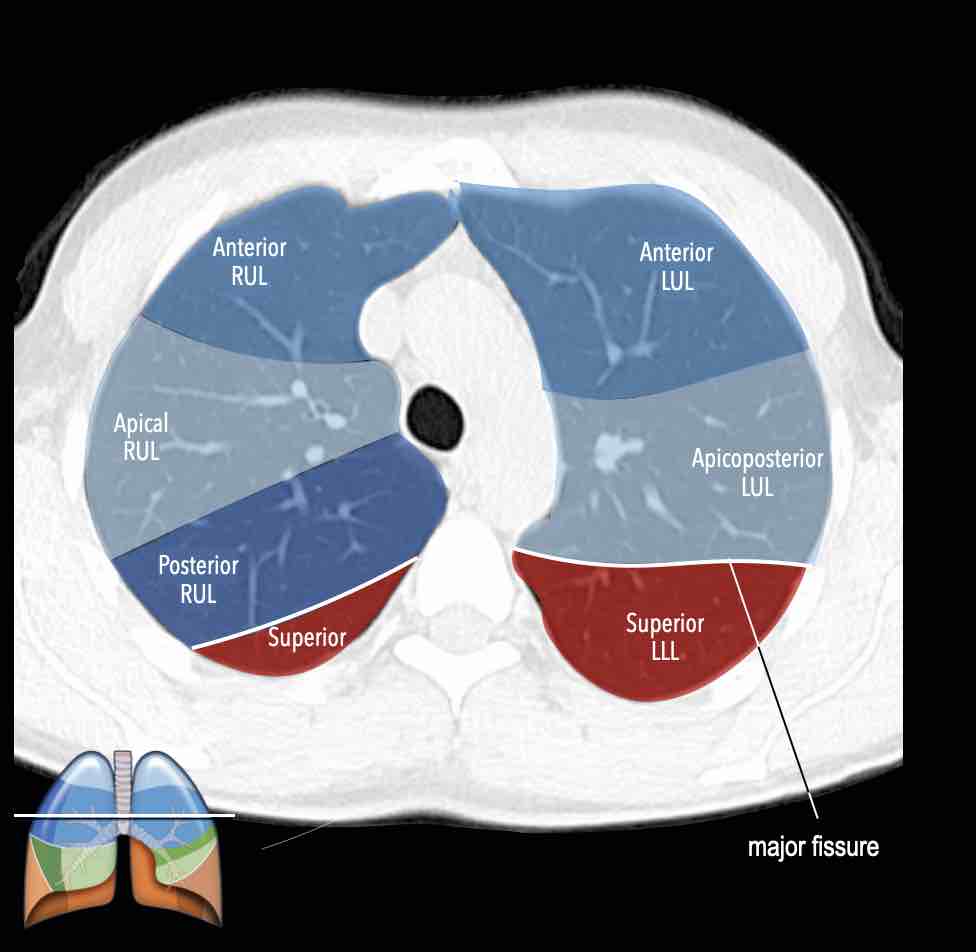

Các phân thùy phổi trên CT

Cuộn qua các hình ảnh để quan sát cách phổi được phân chia thành các phân thùy.